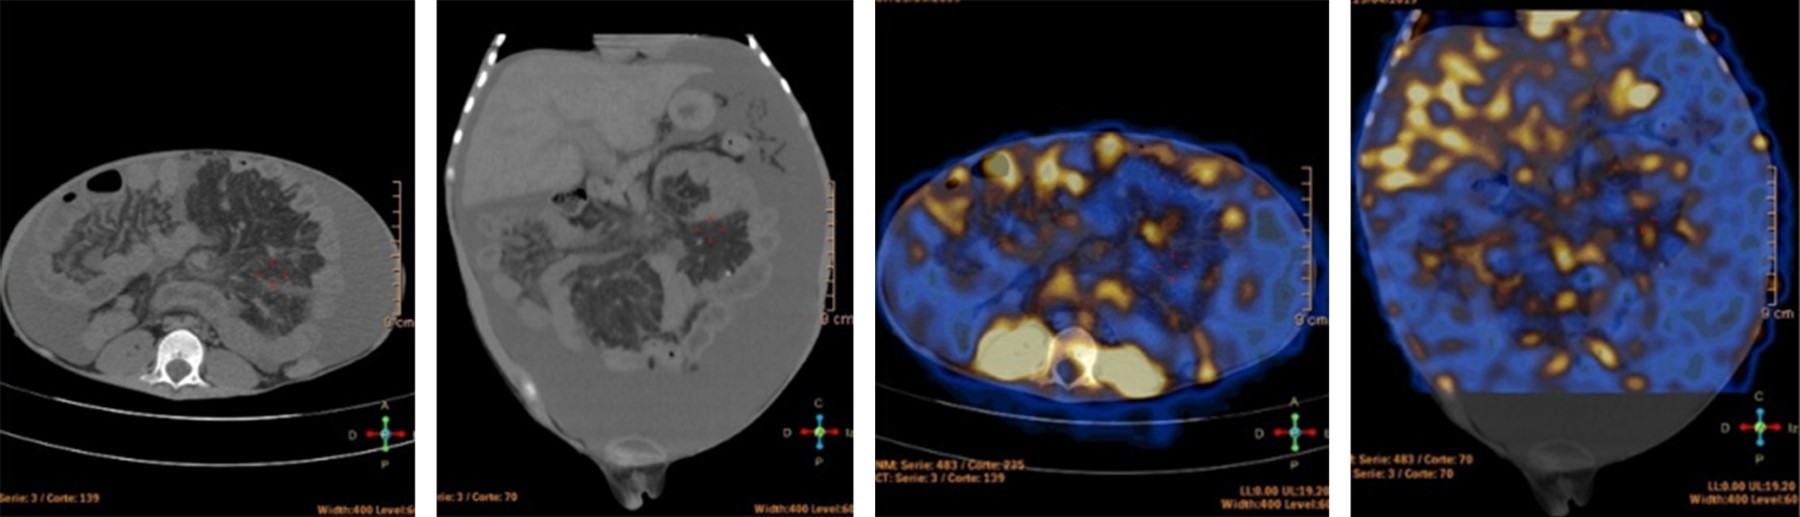

Primary intestinal lymphagiectasia in Klippel-Trénaunay syndrome. Anesthetic management. Case report

Klippel-Trénaunay syndrome with associated primary intestinal lymphangiectasia is a rare entity in pediatrics. It presents with edema due to hypoproteinemia, and in some cases with ascites. The objective is to present a clinical case whose diagnosis was certified by intestinal esdoscopy and biopsy. For refractary ascities, the treatment was surgical, performing peritoneal venous bypass. The anesthetic management of this type of patients has been described in limited reports, so in the present case we emphasize supportive therapy with albumin infusion as the proposed symptomatic treatment for patients with massive drainage of ascities.

Figure 2